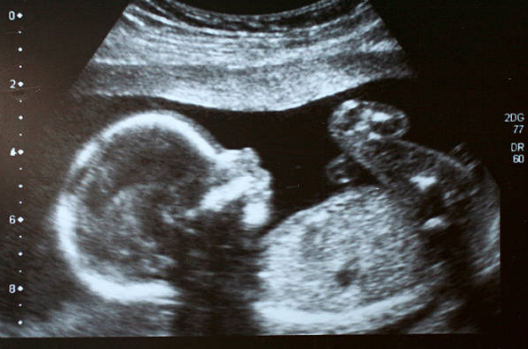

A baby in South America was born with her own twin growing inside of her

The infant, welcomed to a mother in Colombia, was born in February of this year with her partially formed twin inside her abdomen.

The unformed twin was still growing after the baby girl was born.

The baby girl in Colombia, named Itzamara, was initially thought to have a small cyst growing in her liver. However, doctors soon realised she was actually carrying an unformed twin.

The twin, which was surgically removed from baby Itzamara’s abdomen, did not have a heart or a brain. It had its own separate umbilical cord that gained sustenance from the baby’s intestine.

When removed from Itzamara’s body, it had a partially formed head and limbs and measured approximately two inches in length.